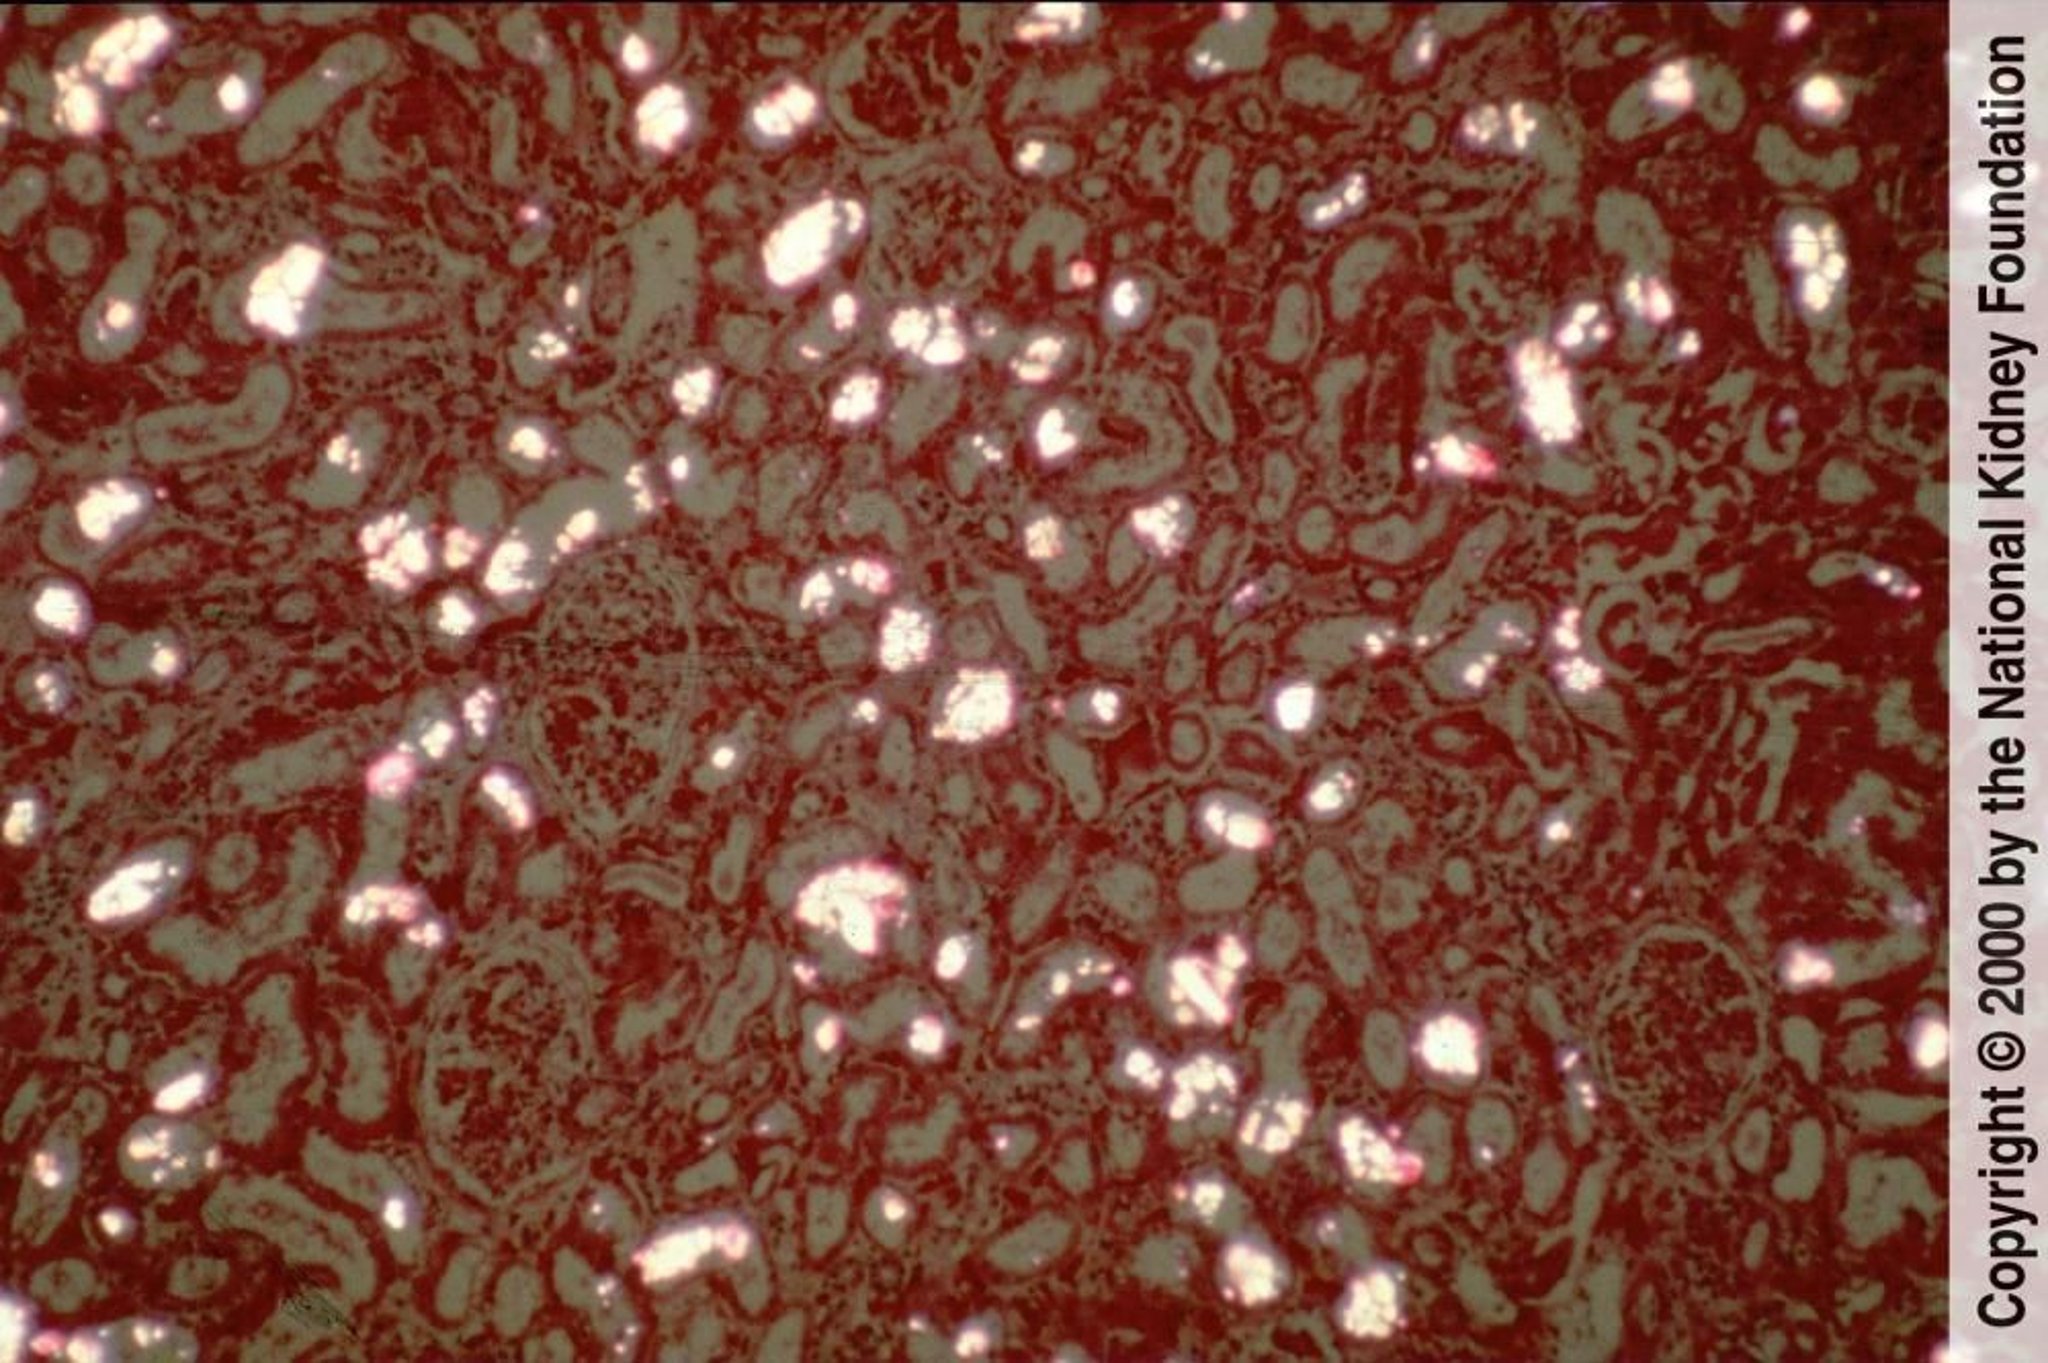

Kalziumoxalatkristalle lagern sich in den Nierentubuli ab und sind unter polarisiertem Licht als doppelbrechende, fächer- oder scheibenförmige Kristalle gut sichtbar (polarisierte Hämatoxylin-Eosin-Färbung, ×100).

Image provided by Agnes Fogo, MD, and the American Journal of Kidney Diseases' Atlas of Renal Pathology (see www.ajkd.org).